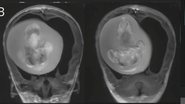

Os pais da menina a levaram ao hospital desconfiados do tramanho da cabeça da criança